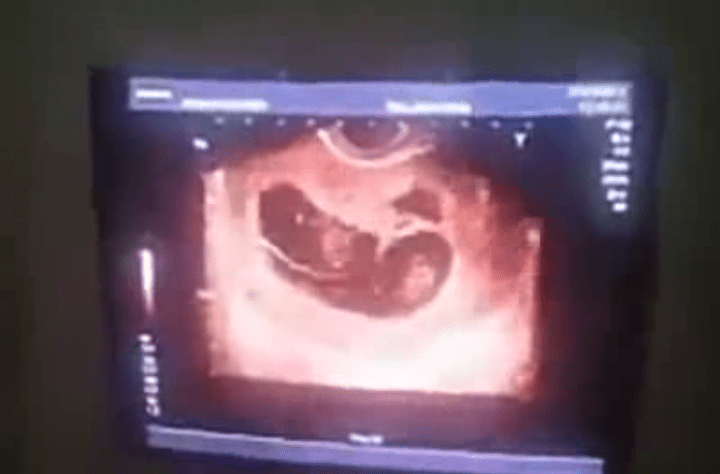

Um vídeo que circula pelas redes sociais mostra a ultrasonografia de uma ‘Suprafetação’.

Esse fenômeno extremamente raro, em que a mãe estando grávida, ocorre quando o corpo da mulher libera outro óvulo dando aos embriões diferentes idades gestacionais.